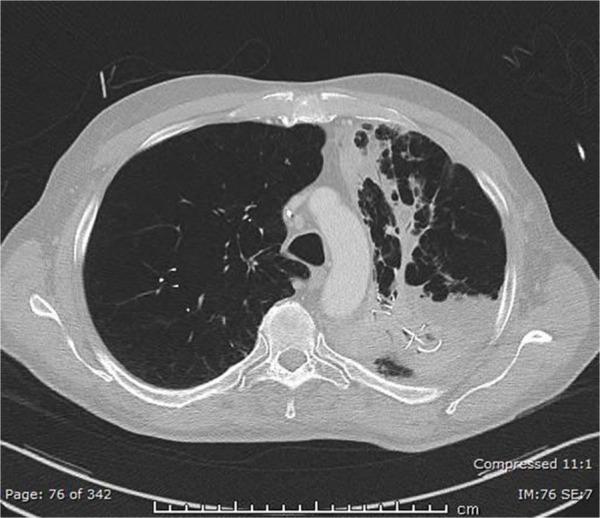

Lung volume reduction coil (LVRC) treatment is established in daily endoscopic lung volume reduction routine. The aim of this study was to evaluate the safety and efficacy of LVRC treatment.

This was a retrospective analysis of 86 patients (male/female: 40/46, mean age: 64±7 years) with severe COPD and bilateral incomplete fissures. A total of 10 coils were unilaterally implanted in a single lobe, and 28 out of 86 patients were treated bilaterally. At 90-, 180-, and 365-day follow-up, changes in pulmonary function test (PFT), 6-minute walk test (6MWT) and modified Medical Research Council (mMRC) dyspnea scale, as well as possible complications, were recorded.

At 90 days, the forced expiratory volume in 1 second did improve (<0.001), but the improvement was not sustained at the 180- and 365-day follow-up (baseline: 0.71±0.21 vs 0.77±0.23 vs 0.73±0.22 vs 0.70±0.18 L). Both vital capacity and residual volume improved significantly (<0.001) at the 90- and 180-day follow-up, but the improvement was lost after 365 days. Total lung capacity decreased at the 90-day follow-up but returned to baseline values at the 180- and 365-day follow-up. 6MWT (=0.01) and mMRC (=0.007) also improved at 90 and 180 days (Δ6MWT of 31±54 and 20±60 m, respectively), but the improvement was also lost at the 365-day follow-up. No significant further improvement was evident at any point in the follow-up after the second procedure. A total of 4 out of 86 patients passed away due to complications. Significant complications in the first 3 months and then at 12 months included the following: severe hemoptysis in 4 (3.5%) and 4 (3.5%) patients, pneumonia requiring hospitalization in 32 (28.1%) and 9 (7.9%) patients and pneumothorax in 7 (6.1%) and 2 (1.7%) patients, respectively. Milder adverse events included self-limited hemoptysis, pneumonias, or COPD exacerbations treated orally.

LVRC improved PFT, 6MWT and mMRC initially, but the improvement was lost after 365 days. Furthermore, we observed 4 deaths and significant severe complications, which need to be further elucidated.